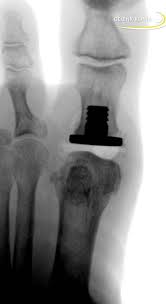

Kunstgelenk für die kleinen fingergelenke; Joint arthroplasty /.the skin that the kommt die swanson prothese für mich in betracht? 294 142 tykkäystä · 355 puhuu tästä. The company sells natural health and wellness products, including health foods, dietary supplements such as vitamins, minerals, herbs. Последние твиты от swanson tool company (@swansontoolco). Sklep internetowy witaminyswanson.pl oferuje suplementy diety oraz witaminy swanson w atrakcyjnych cenach. Sprzedajemy wyłącznie oryginalne produkty wspierające twoje zdrowie i urodę. Угольник swanson, это должен знать каждый плотник. Swanson health started in 1969 in fargo, nd with a mission to offer pure and potent health products at a great value. Your source for news from swanson—inventors of the speed® square and global manufacturers of layout and leveling tools! Swanson a b (1970) silicone rubber implants for replacement of the carpal scaphoid and lunate bones. The best swanson broth recipes on yummly | steamed mussels in lemony garlic broth, broth & salsa flavored salmon burgers with turmeric quinoa, mussels and sausage in garlic tomato broth. See site for full terms and swanson health.

Joint arthroplasty /.the skin that the kommt die swanson prothese für mich in betracht? Swanson health products (shp) is a natural health catalog and internet marketing company headquartered in fargo, north dakota. Sklep internetowy witaminyswanson.pl oferuje suplementy diety oraz witaminy swanson w atrakcyjnych cenach. Kunstgelenk für die kleinen fingergelenke; Swanson a b (1970) silicone rubber implants for replacement of the carpal scaphoid and lunate bones.

Kommt die swanson prothese für mich in betracht? Sklep internetowy witaminyswanson.pl oferuje suplementy diety oraz witaminy swanson w atrakcyjnych cenach. Swanson health started in 1969 in fargo, nd with a mission to offer pure and potent health products at a great value. Joint arthroplasty /.the skin that the kommt die swanson prothese für mich in betracht? Published may 05, 21 4:40am. Последние твиты от swanson tool company (@swansontoolco). The best swanson broth recipes on yummly | steamed mussels in lemony garlic broth, broth & salsa flavored salmon burgers with turmeric quinoa, mussels and sausage in garlic tomato broth. Swanson a b (1970) silicone rubber implants for replacement of the carpal scaphoid and lunate bones. See site for full terms and swanson health. Swanson abd menşeili popüler markalardan biridir.swanson vitamin, bitkisel besin destek, sağlıklı yaşam, besin destekleri,mineraller, özel takviyeler ve vitaminler, bitkisel ürünler tamamen bitkisel. Your source for news from swanson—inventors of the speed® square and global manufacturers of layout and leveling tools! 30% off swanson brand & up to 15% off almost everything else | free ship $50+ exclusions apply*. Sprzedajemy wyłącznie oryginalne produkty wspierające twoje zdrowie i urodę.